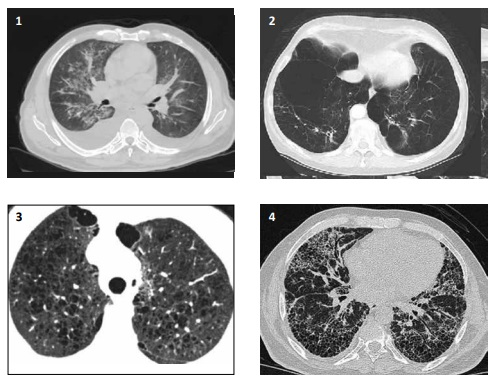

Uma mulher de 32 anos de idade, com antecedentes de ansiedade e enxaqueca, compareceu ao pronto-socorro

trazida por uma viatura do SAMU acompanhada por uma amiga, com relato de cefaleia holocraniana intensa, que teve início

duas horas antes, além de vômitos intensos, mal-estar e rebaixamento do nível de consciência durante o transporte. A seguir,

consta a tomografia computadorizada do crânio.

Assinale a alternativa adequada.